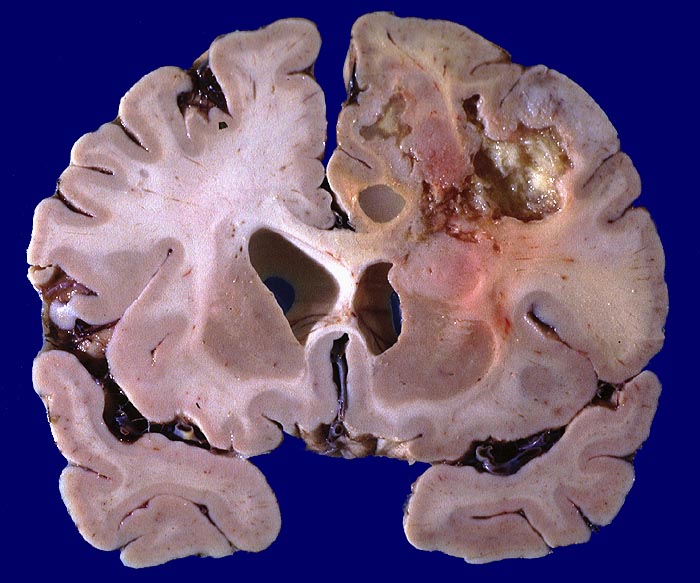

Lokalisation:

Bevorzugte Lokalisationen sind das Marklager des Frontal- und Temporallappens. Glioblastome des Hirnstammes sind selten und betreffen meist Kinder. Von dort breiten sie sich oft über den Balken schmetterlingsförmig auf die Gegenseite aus. Weniger als 5% der Tumoren wachsen multizentrisch. Eine Aussaat in den Subarachnoidalraum mit Metastasierung über den Liquor findet sich selten. Noch rarer sind hämatogene Metastasen in extraneurale Organe.

Morphologie:

Die Schnittfläche ist auffallend bunt. Dies ist bedingt durch ein Nebeneinander von graurotem vitalem Tumorgewebe, gelben Nekrosen, roten Einblutungen und gelegentlich grünlichen Gallertzysten.